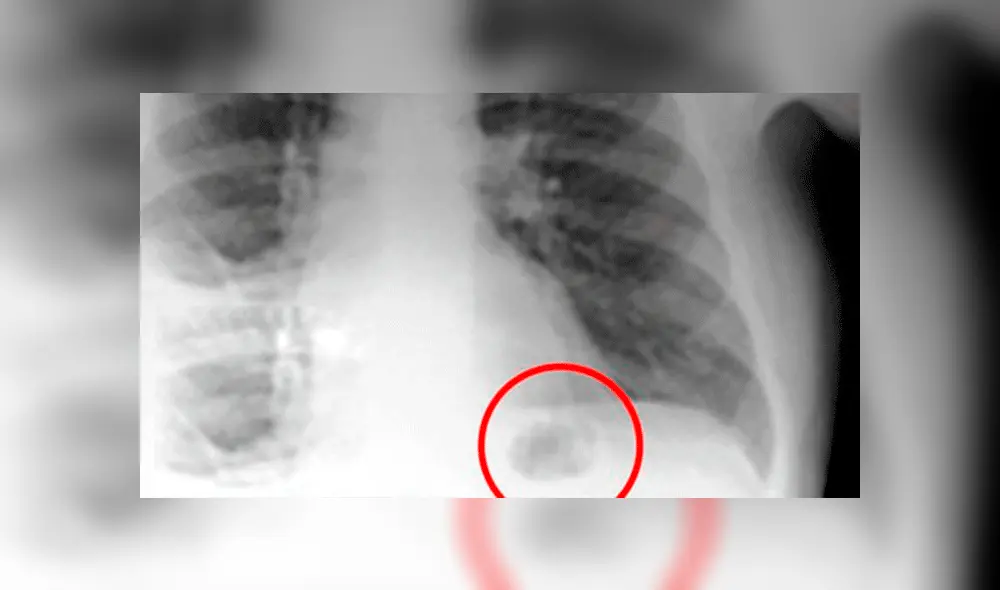

Creyó que una mancha en sus pulmones era cáncer, pero se llevó tremenda sorpresa al descubrir la verdad [FOTO]